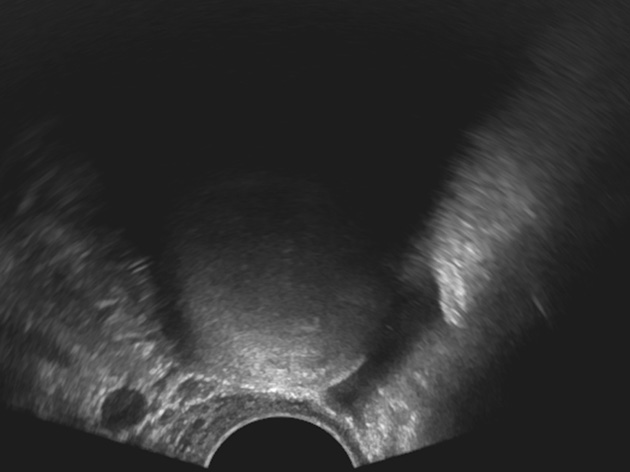

К «практически наверняка доброкачественным» относятся образования, имеющие «классическую» эхографическую картину доброкачественного образования (простая и однокамерная киста, геморрагическая киста, эндометриома, дермоидная киста и фиброма) (рис. 1–6). Понятие однокамерной кисты относительно новое и подразумевает наличие в полости кисты ≥1 неполной перегородки, локальных утолщений на стенке высотой до 3 мм, внутренних эхо в полости (рис. 2). Одиночная тонкая (≤3 мм) перегородка в полости кисты считается доброкачественной находкой [22].

Рис. 3. Геморрагическая киста яичника. Киста с сетчатым рисунком и сгустком в виде эхогенного компонента с ангулярными контурами в полости

Fig. 3. Hemorrhagic ovarian cyst: a cyst with a mesh pattern and a blood clot presenting in the form of an echogenic component with angular contours in the cavity

Рис. 4. Эндометриома. Киста с гомогенной эхопозитивной взвесью в полости (эхогенность «матовое стекло»)

Fig. 4. Endometrioma: a cyst with homogeneous echo-positive suspension in the cavity (ground glass echogenicity)